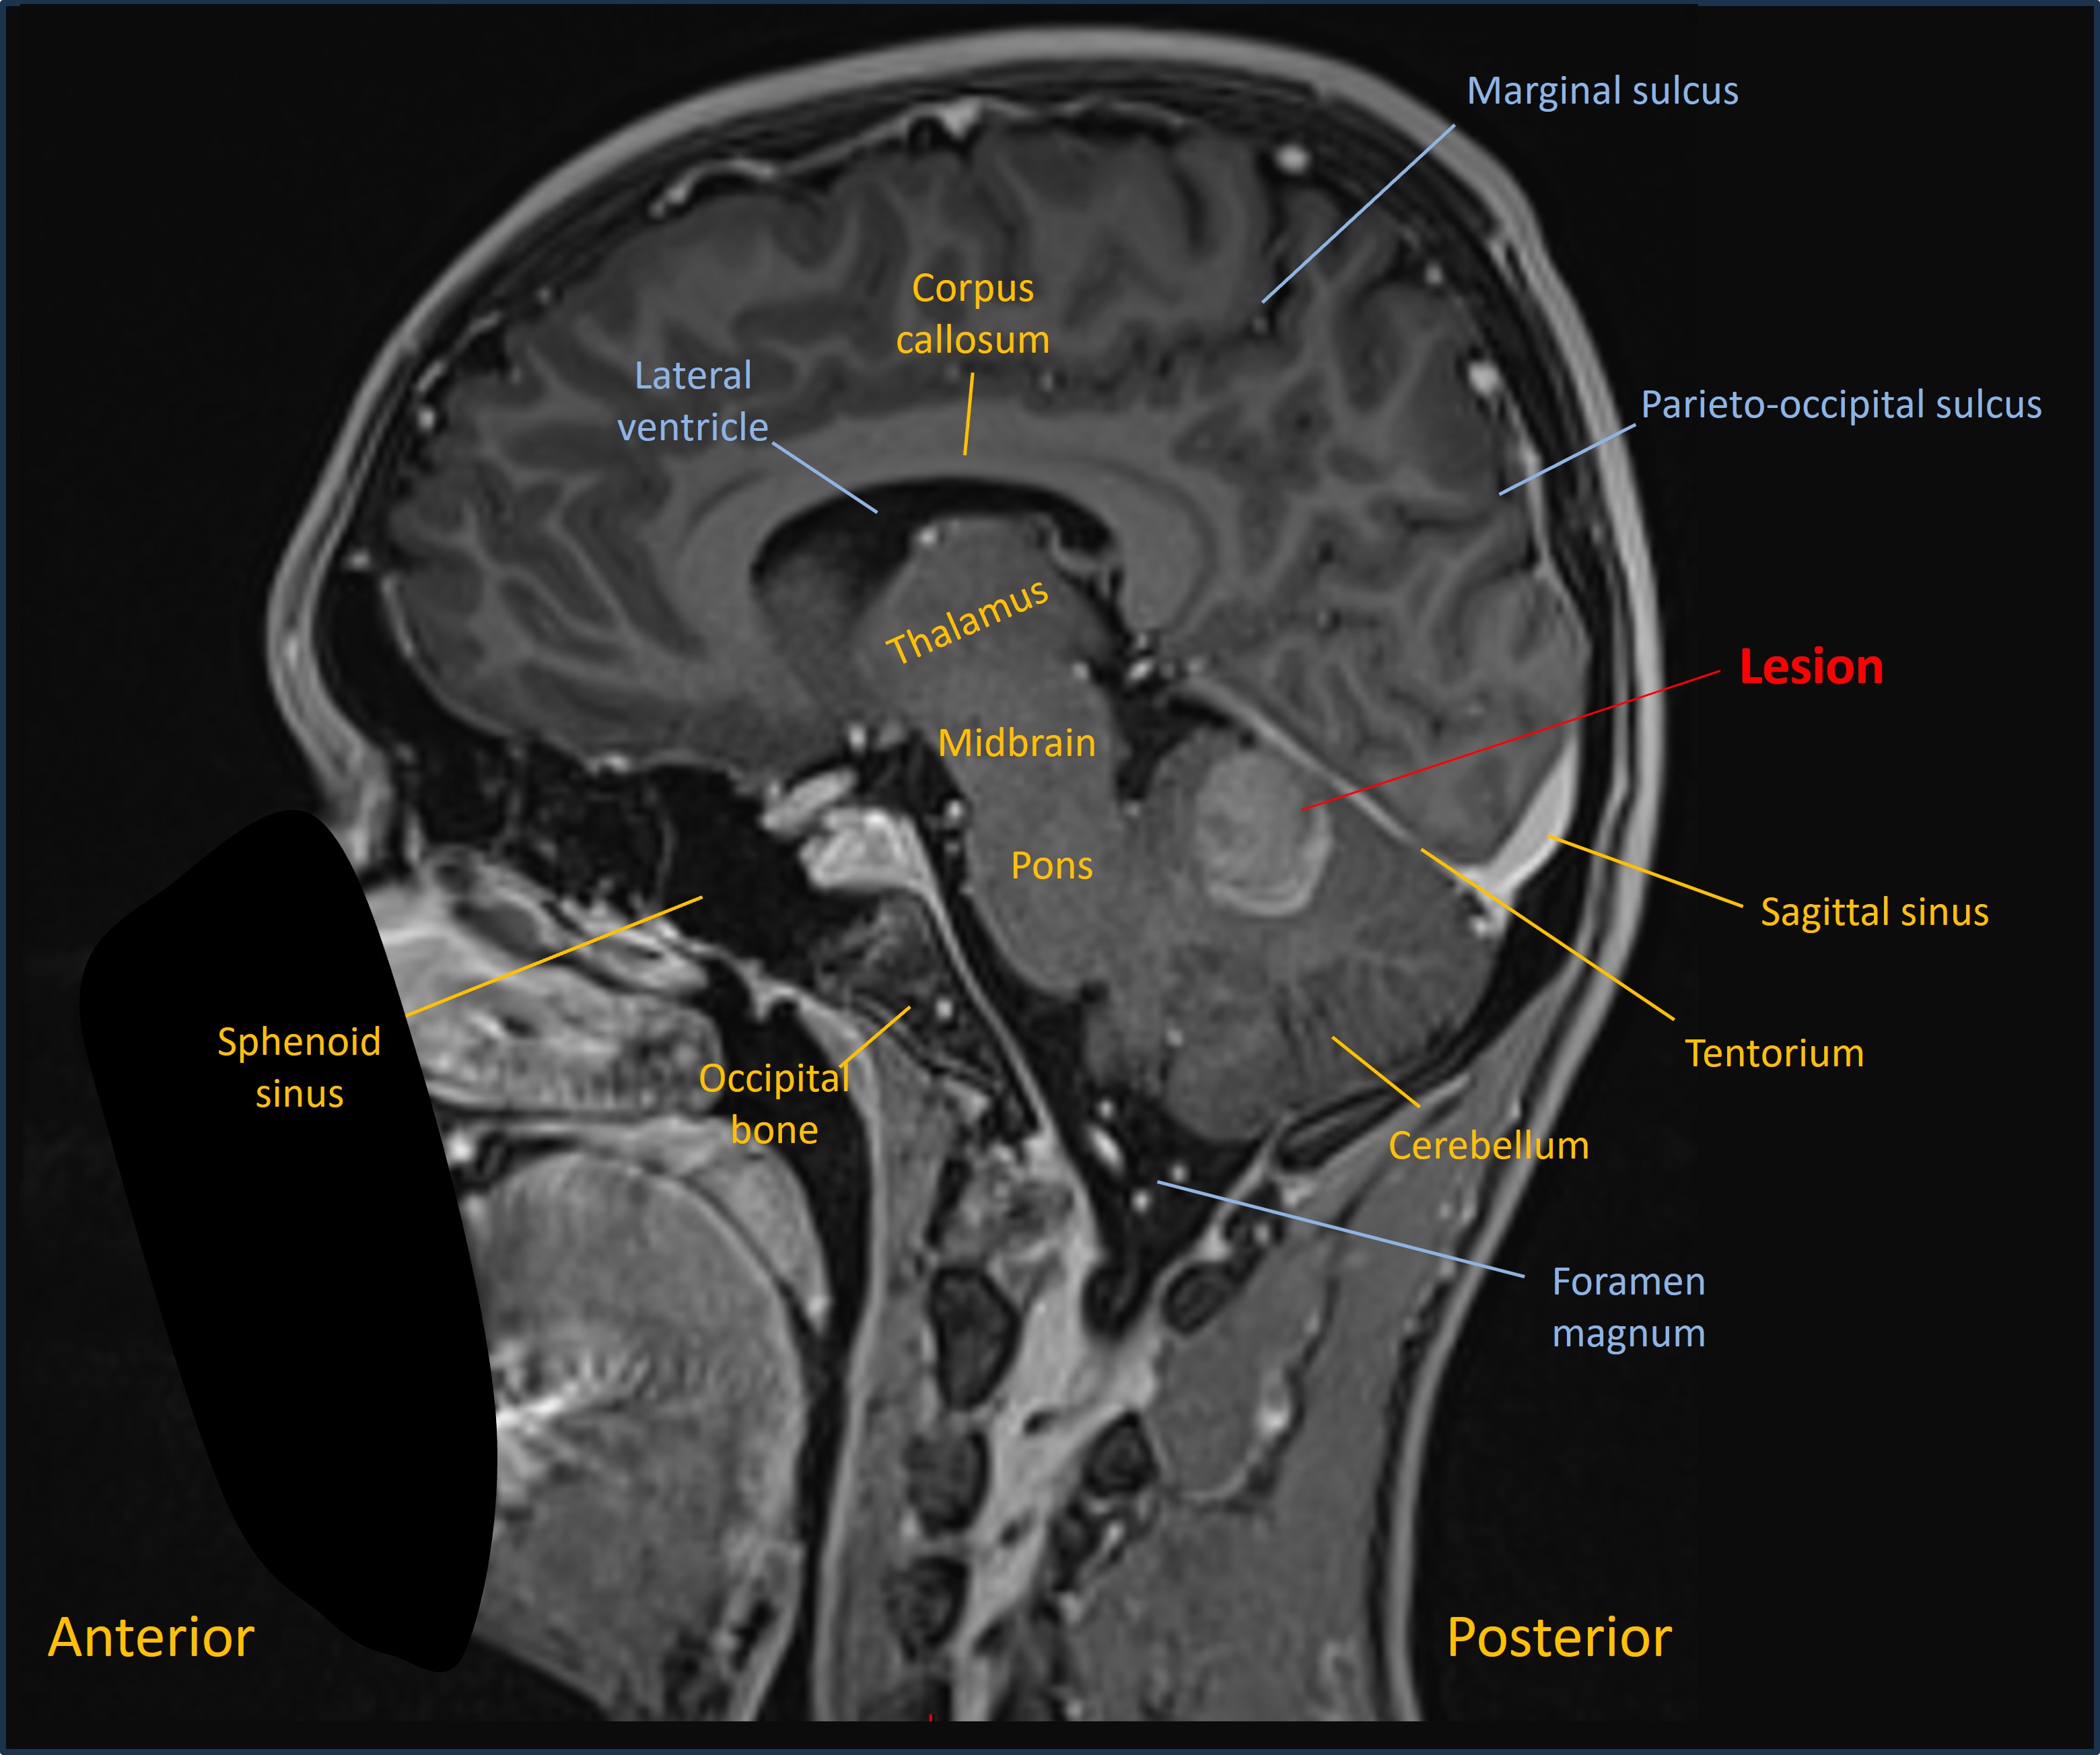

MRI showed a lesion in the right cerebellar hemisphere, with appearances suggestive of a recent haemorrhage surrounding an underlying lesion - shown on the sagittal T1 and axial T2 MRI images below: .

Sagittal MRI

Axial MRI

A differential diagnosis was suggested, including tumour, but the imaging was thought most likely to reflect an underlying cavernoma.